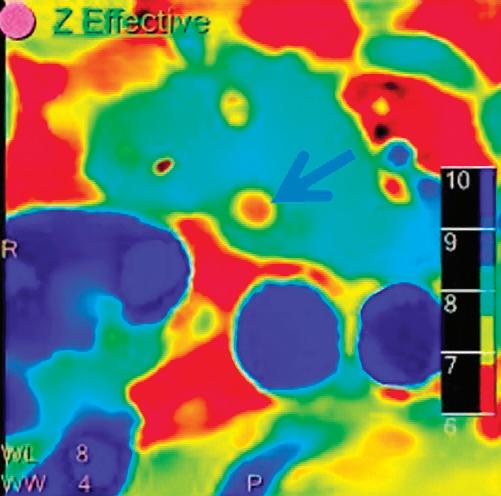

Z Effective (Zeff)

Effective atomic number. Each voxel is set to a value in the range 5 to 30 representing the effective atomic number of that voxel. Z effective of air is set to zero. For reference, Z effective of water is 7.4, Z effective of cortical bone is 13.2, and Z effective of fat is 5.9. Z effective maps are very sensitive to materials characteristics (Figure 3) and can also be used to display perfusion maps and to identify very subtle perfusion deficits (Figure 2b). The accuracy measured on a Gammex phantom with iodine, calcium, and soft tissue inserts show that the majority of Z effective values are within 0.2 Z effective units and are consistent between 120 and 140 kVp scans.21